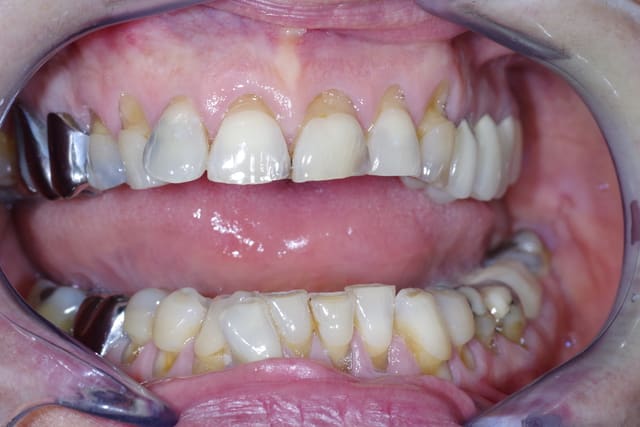

Je souhaiterais savoir comment vous gérer ces cas de mylolyses/érosions importantes sur les antérieures.

Pour le cas iconographié, je pensais à des facettes (histoire de donner une seconde jeunesse au sourire), mais je me demande comment réaliser mes préparations, s'il faut combler au compo pour éviter de surtailler autour, etc.

Avant d'envisager la moindre facette, il va falloir je pense revoir l'occlusion de ta patiente: courbe de Spee foirée à gauche, parafonction 21,22, vestibulo-version 12 suite DDM inf.

Gros point positif ici: la patiente semble avoir une hygiène impeccable et dégage assez peu les collets au sourire, d'où une certaine facilité à gérer l'esthétique "rose".

Après pour la partie technique pure au niveau antérieur, tout dépend de l'état d'usure palatine, et de lq stabilisation du bruxisme/parafonction, (comme demandé plus haut par GP) une photo occlusale peut nous guider pour connaître la meilleur thérapeutique à adopter, et l'éventail est large: du simple composite à la couronne périphérique en passant par la facette bilaminaire (au fait Gp se serait sympa de partager ce genre de cas avec les Nonoliens ;-)).

Ma question est purement technique. En palatin on ne note pas d'usure. Comment gérer la profondeur à rattraper, sur 23 par exemple, et comme tu l'indiques, Cingulum, quid de la qualité du collage sur ce type de dentine sclérosée? Avez-vous des trucs et/où astuces ?